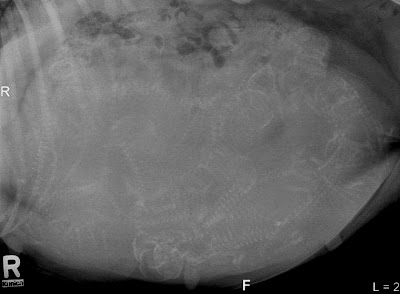

| Bella's x-ray. How many puppies do you think she will have? |

Bella

abdomen seems to expand daily. She is now measuring approximately 36.25 inches (92 cm). Today we had her tummy x-rayed to see just how many puppies she

is carrying which will help prepare us for the big event. That day (or night)